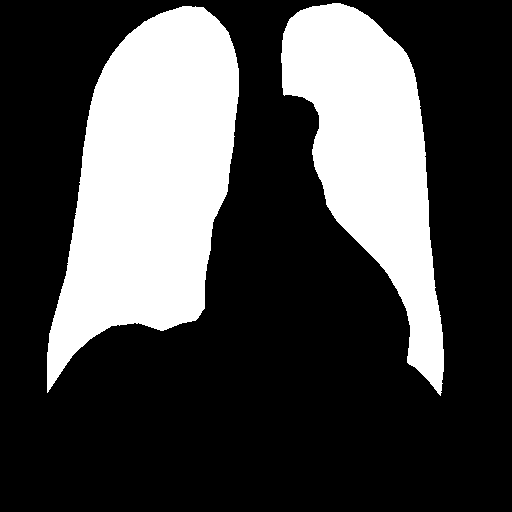

After heart and lung masks are computed, we performed dilation followed by erosion to fill holes in output mask [18], then we find the connected components of prediction masks (Figure 3).

From the lung mask, we chose the two largest connected components and disregarded others as noise. The connected component with a lower x-axis coordinate is designated as the left lung mask and the other as the right lung mask. From the heart mask, we chose the connected component larger than a given threshold and closest to the center and designate it as the heart mask.